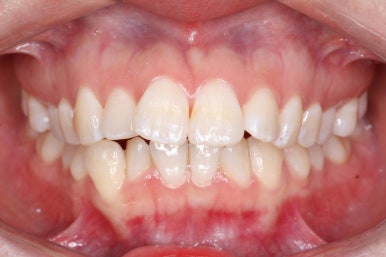

중앙선도 잘 맞고 교합도 잘 마무리되었습니다.

이 뽑은 자리가 다시 벌어지지 않게 앞니가 다시 틀어지지 않게 유지철사를 부착하고 마무리를 하였습니다.

전후 비교해 보겠습니다.

중앙선, 교합, 뻐드러짐 모두 좋아졌고 이를 뽑고 교정했지만 발치 공간이 남지 않고 잘 마무리 되었습니다.